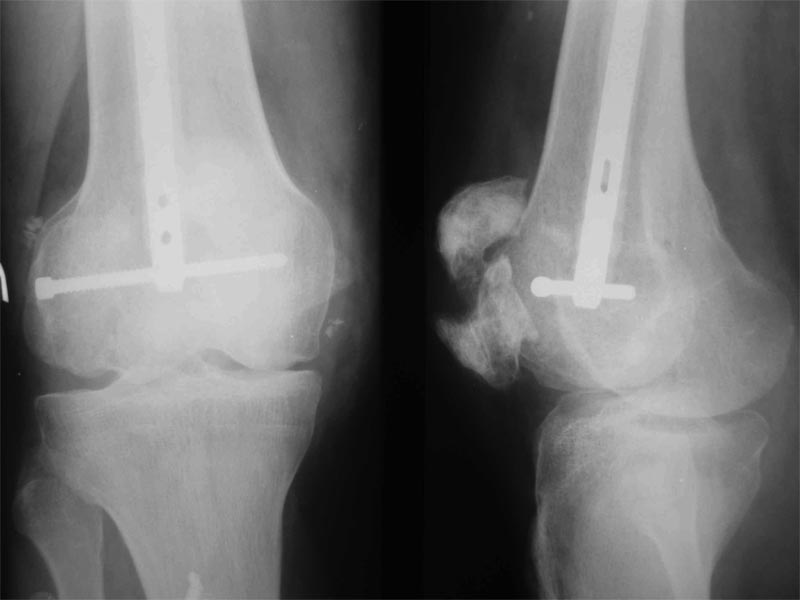

Уважаемые коллеги! Пациент получил травму около 1 года назад, выполнялся остеосинтез по поводу переломов лучевой, бедренной, плечевой костей. Обратился в связи с выраженной контрактурой в коленном суставе (сгибание 10-15 град)и практически отсуствием самостоятельного отведения плеча. Снимки представлены. Планируем выполнить реостеосинтез плеча (скорее всего этим же стержнем, так как другого нет) с коррекцией положения отломков в проксимальном отделе и сближением отломков в области диафиза. По надколеннику пока одна идея - его удаление. Хотелось бы услышать мнение и советы участников форума. - необходима ли будет костная пластика в области диафиза плеча? - адекватен ли по Вашему мнению реостеосинтез стержнем? - какая тактика в отношении ротационной манжеты? - приведет ли удаление надколенника и релиз сустава к существенному улучшению функции? Спасибо.

1. Надколенник сломался при первичной травме, и первоначально фиксировался внешним аппаратом.

Качественные последние рентгенограммы приложите, пожалуйста,если хотите, чтобы Вам помогли, т.к. по представленным можно только догадываться, что там с проксимальным отделом плеча. Кстати какой возраст пациента?

- удаление надколенника не приведет к улучшению функции.

А вот его реконструкция реально сложная задача, т.к. проблема не столько в переломе,сколько в фиброзе. Здесь 4 опции:

1) ничего не делать, оставить так как есть

2) одноэтапная реконструктивная операция: артролиз, V-Y пластика 4-х главной мышцы, остеосинтез надколенника, ранняя реабилитация

3) двухэтапная операция: первый этап - препателлярное вытяжение с целью растянуть мышцу и сблизить отломки надколенника, второй этап - артролиз, остеосинтез надколенника, ранняя реабилитация

4) протезирование